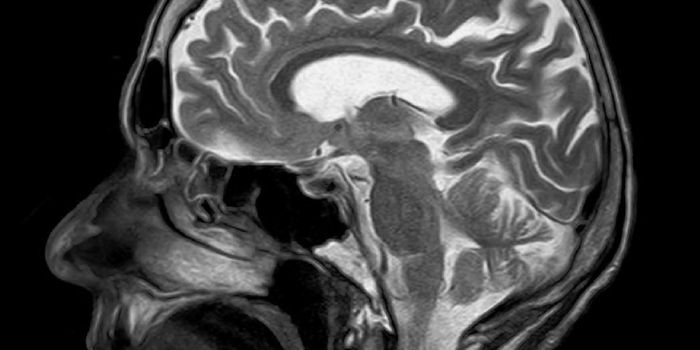

NOV 18, 2015Clinical & Molecular DXThe human brain may not look like much, composed of about three pounds of soft mushy matter. But we all know that our br ...

NOV 19, 2015Clinical & Molecular DXCould a shorter brain fold be diagnostic of hallucinations associated with schizophrenia? After analyzing the MRI scans ...